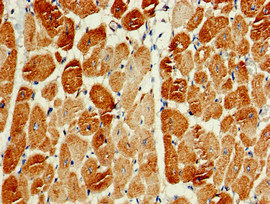

Immunohistochemistry of paraffin-embedded human heart tissue using CSB-PA854108LA01HU at dilution of 1:100

Immunohistochemistry of paraffin-embedded human skeletal muscle tissue using CSB-PA854108LA01HU at dilution of 1:100